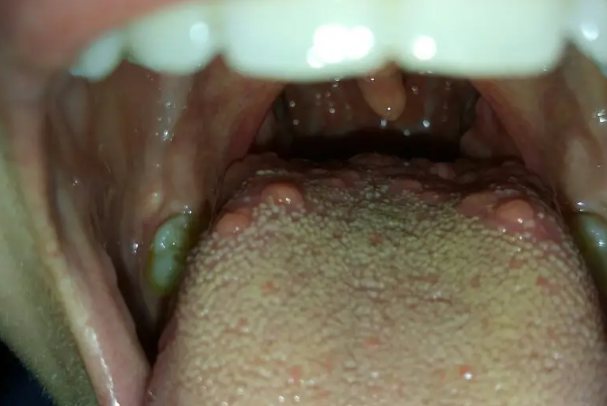

正常咽喉舌根疙瘩为轮廓乳头、舌扁桃体。

轮廓乳头主要分布在舌根靠近咽喉部位,呈人字形排列,是一个比较重要的味觉器官。舌扁桃体是指位于舌根的淋巴组织集团,呈颗粒状聚积于舌根部。

1.轮廓乳头

轮廓乳头在舌乳头中体积最大,数目最少,约8~12个,沿界沟前方排成一列,呈矮柱状,高约1~1.5mm,直径约1~3mm,每个乳头的四周均有深沟环绕,轮廓沟外的舌黏膜稍隆起,形成乳头的轮廓结构,此乳头表面上皮有角化。但乳头的侧壁即轮廓沟壁上皮无角化,其上皮内有许多染色浅的卵圆形小体,称味蕾。

2.舌扁桃体

舌扁桃体呈颗粒状聚积于舌根部,周围及底部有一层纤维组织与舌体相隔,但无明显的被膜,其表面被覆复层鳞状上皮,有隐窝状凹隐。鳞状上皮下方有密集的淋巴组织,内含淋巴滤泡。淋巴样组织被纤维组织分隔成灶状,并与周围的纤维组织、脂肪组织、浆液粘液腺和骨骼肌纤维融合。